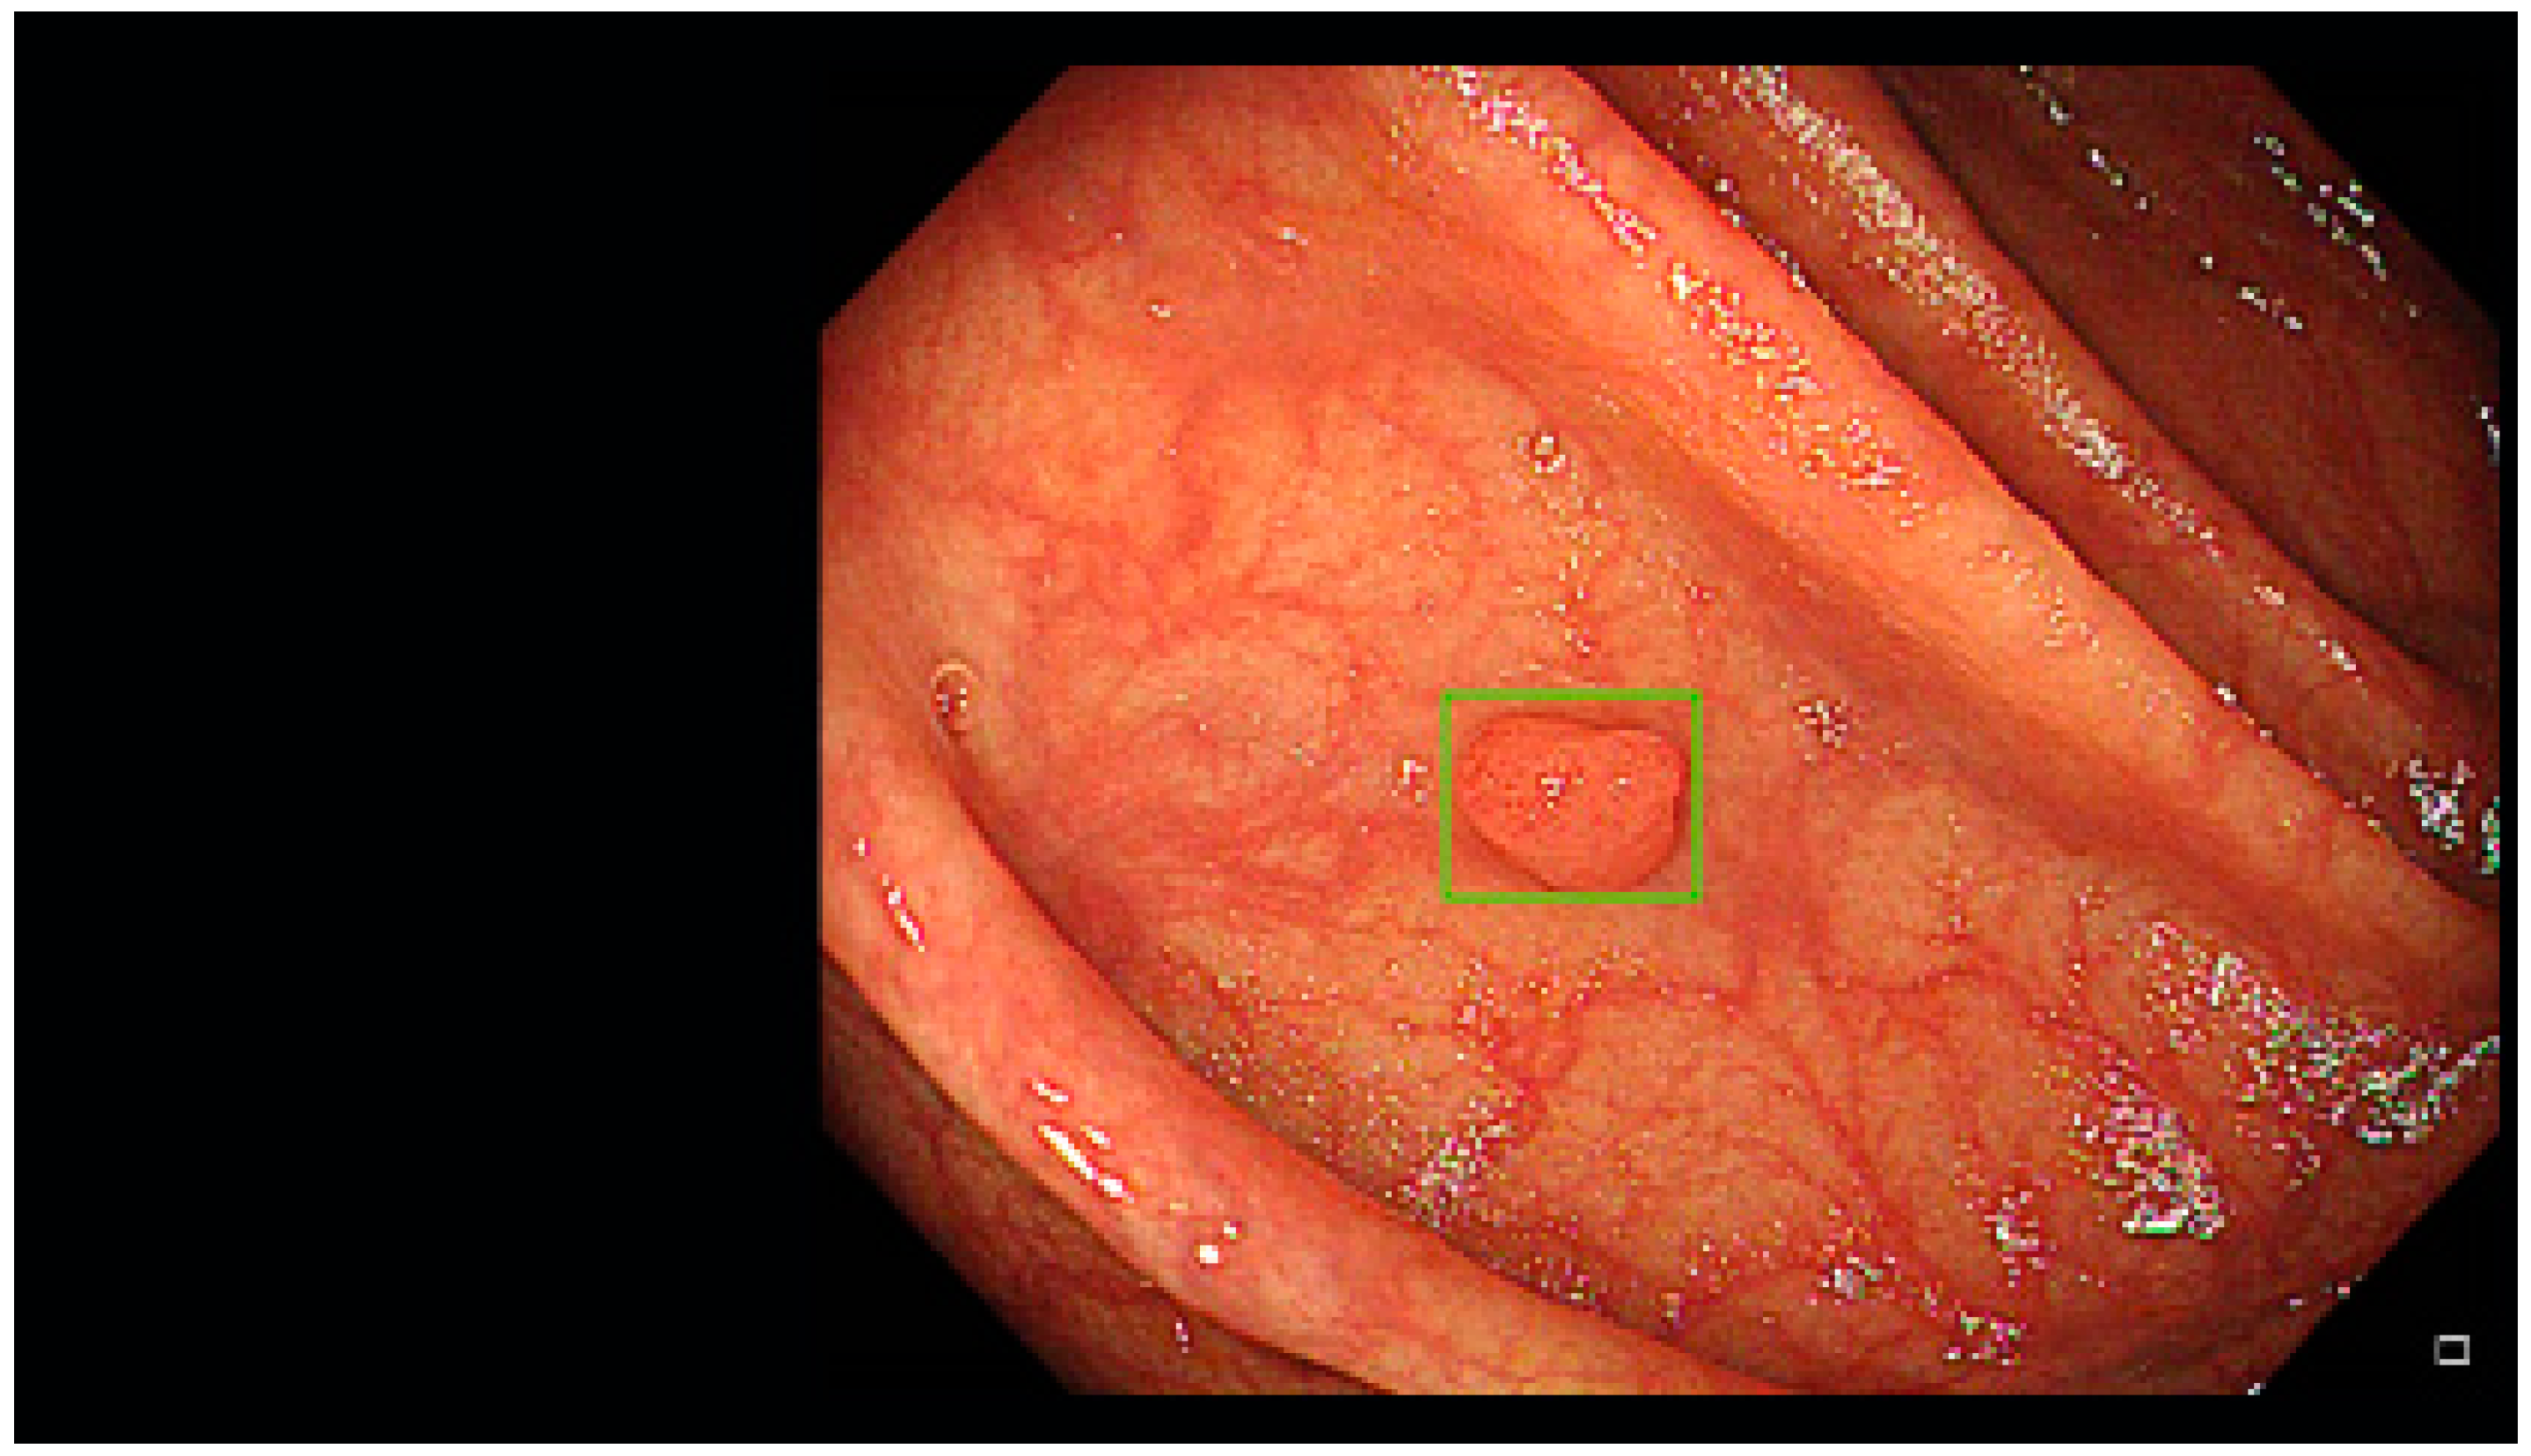

- Misawa, M.; Kudo, S.-E.; Mori, Y.; Cho, T.; Kataoka, S.; Yamauchi, A.; Ogawa, Y.; Maeda, Y.; Takeda, K.; Ichimasa, K.; et al. Artificial Intelligence-Assisted Polyp Detection for Colonoscopy: Initial Experience. Gastroenterology 2018, 154, 2027–2029. [Google Scholar] [CrossRef] [PubMed]

- Klare, P.; Sander, C.; Prinzen, M.; Haller, B.; Nowack, S.; Abdelhafez, M.; Poszler, A.; Brown, H.; Wilhelm, D.; Schmid, R.M.; et al. Automated polyp detection in the colorectum: A prospective study (with videos). Gastrointest. Endosc. 2019, 89, 576–582.e1. [Google Scholar] [CrossRef]